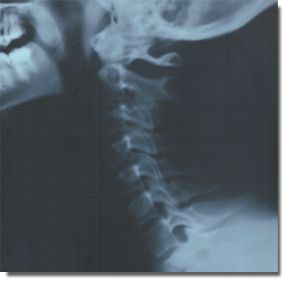

discs and the ligaments running along the spine. These include the anterior longitudinal ligament, posterior longitudinal ligament, intraspinous ligaments and potentially others. Muscles are almost always injured and become inflamed, particularly the Longus Colli and Sternocleidomastoid muscles. Evulsion injuries are common. The characteristic radiological finding after a car accident is the Military Neck (which is also referred to as Stage 1 Degeneration) in which the cervical spine has lost its natural cure and can even become reversed. In many cases we also see a disruption of George’s Line, meaning the vertebrae are no longer exhibiting a smooth continuous relationship one on top of the other. This indicates severe ligament damage, disc injury and spinal instability. This is a serious finding and needs greater therapeutic attention.

Once someone has had a whiplash injury the status of their spine should be periodically monitored with x-ray to watch for signs of degeneration.